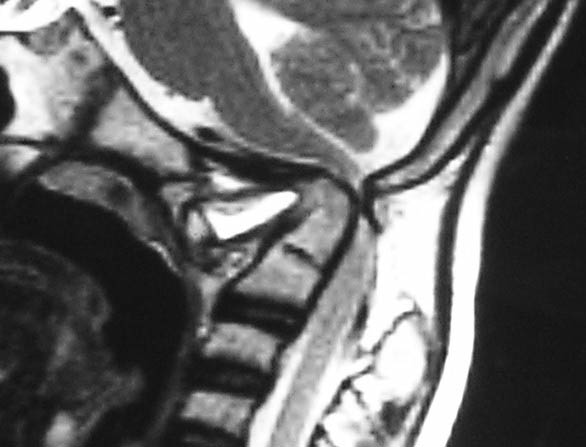

Craniovertebral Junction Anomaly

The junction of the skull with the neck is called craniovertebral junction. This is the site for a number of pathologies, that can have severe neurological problems and can be potentially life threatening. Diagnosis is achieved by CT and MRI, and treatment involves decompression and provision of stability by metallic implants.